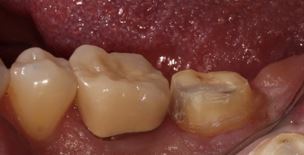

Subgingival margins are a common clinical challenge. In these cases, deep margin elevation can be a useful technique to help restore teeth to their proper form and function.

How does deep margin elevation work? Once the subgingival aspect of the prep is completed, a matrix is placed and tightly adapted to the tooth structure. A wedge is often not placed, enabling the margin elevation to reproduce an appropriate emergence profile.

The tooth is treated using the etching and bonding protocol (for composite) or a tooth conditioner (for glass ionomer or RMGI). The material can flow passively against the matrix until it is at an equigingival or supragingival location.